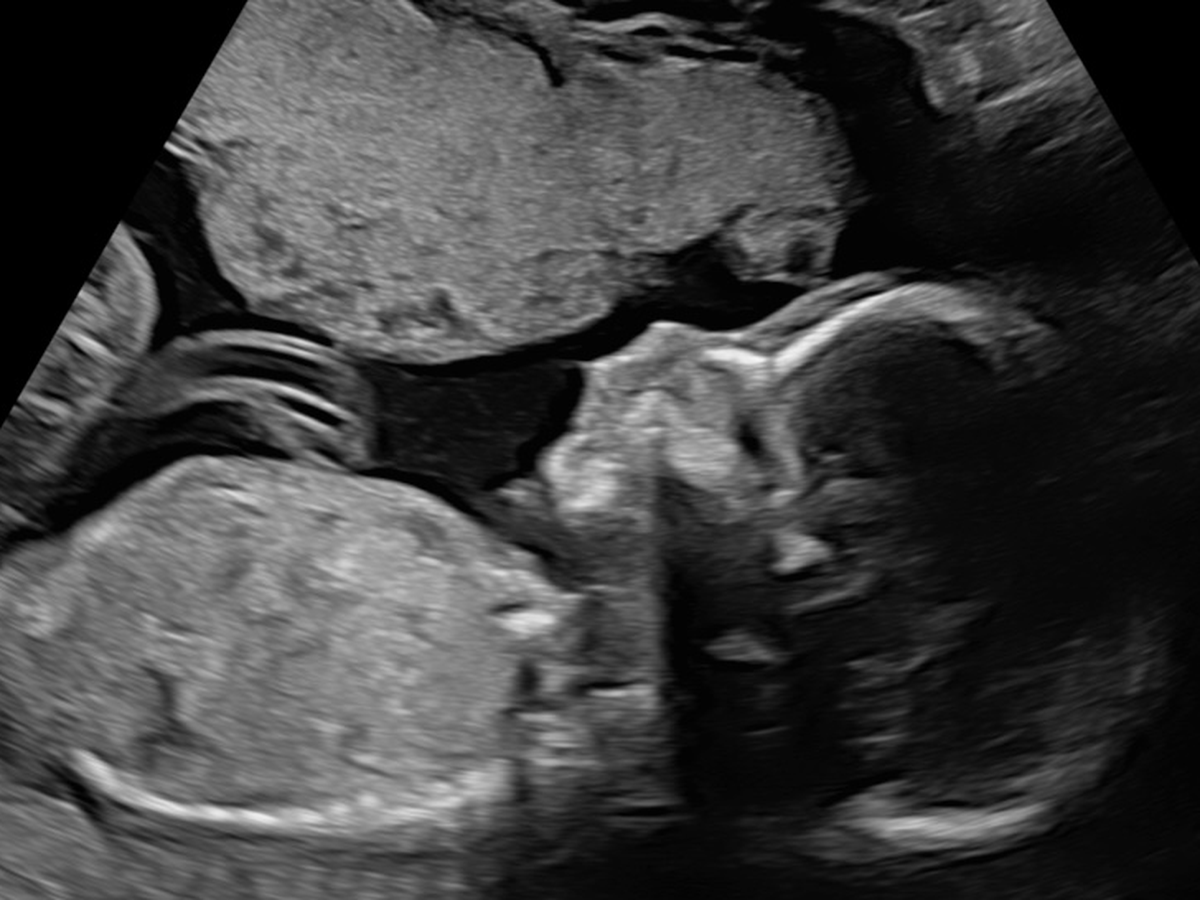

On April 9th, we received devastating news that our unborn baby was diagnosed with a Congenital Diaphragmatic Hernia, a rare and life threatening condition. CDH, is causing her organs to migrate into the chest cavity. Due to this, her heart is on the right side of her chest and her lungs have limited space to develop.